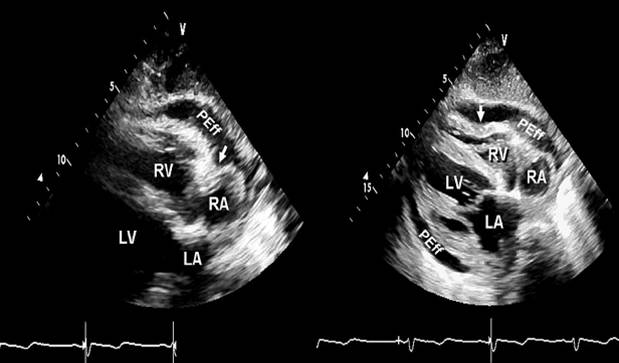

M型:室间隔运动随呼吸变化 typical CP

心脏变形,双房大,

缩窄性心包炎,多普勒血流频谱

缩窄性心包炎

类风关,缩窄

心脏变形,包裹性心包积液